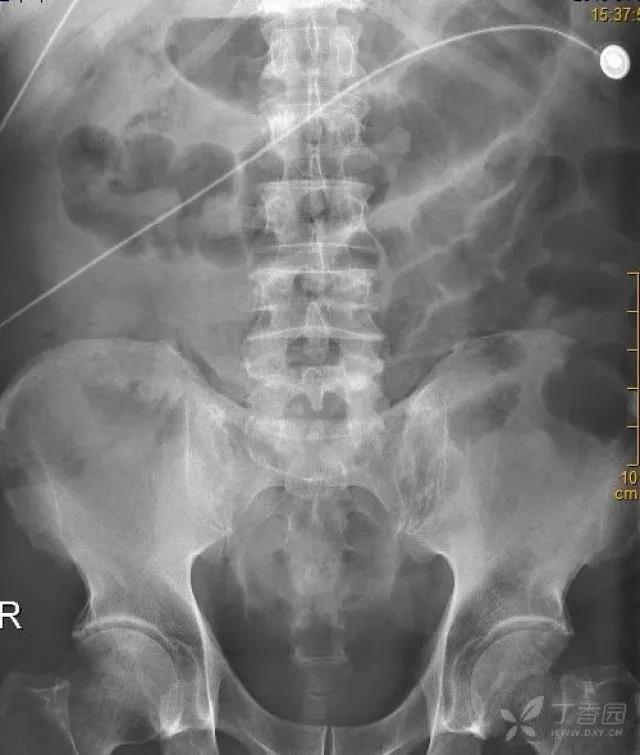

急诊平扫 CT:

看看增强 CT 图片,能发现问题吗?

动脉期:

门静脉期: